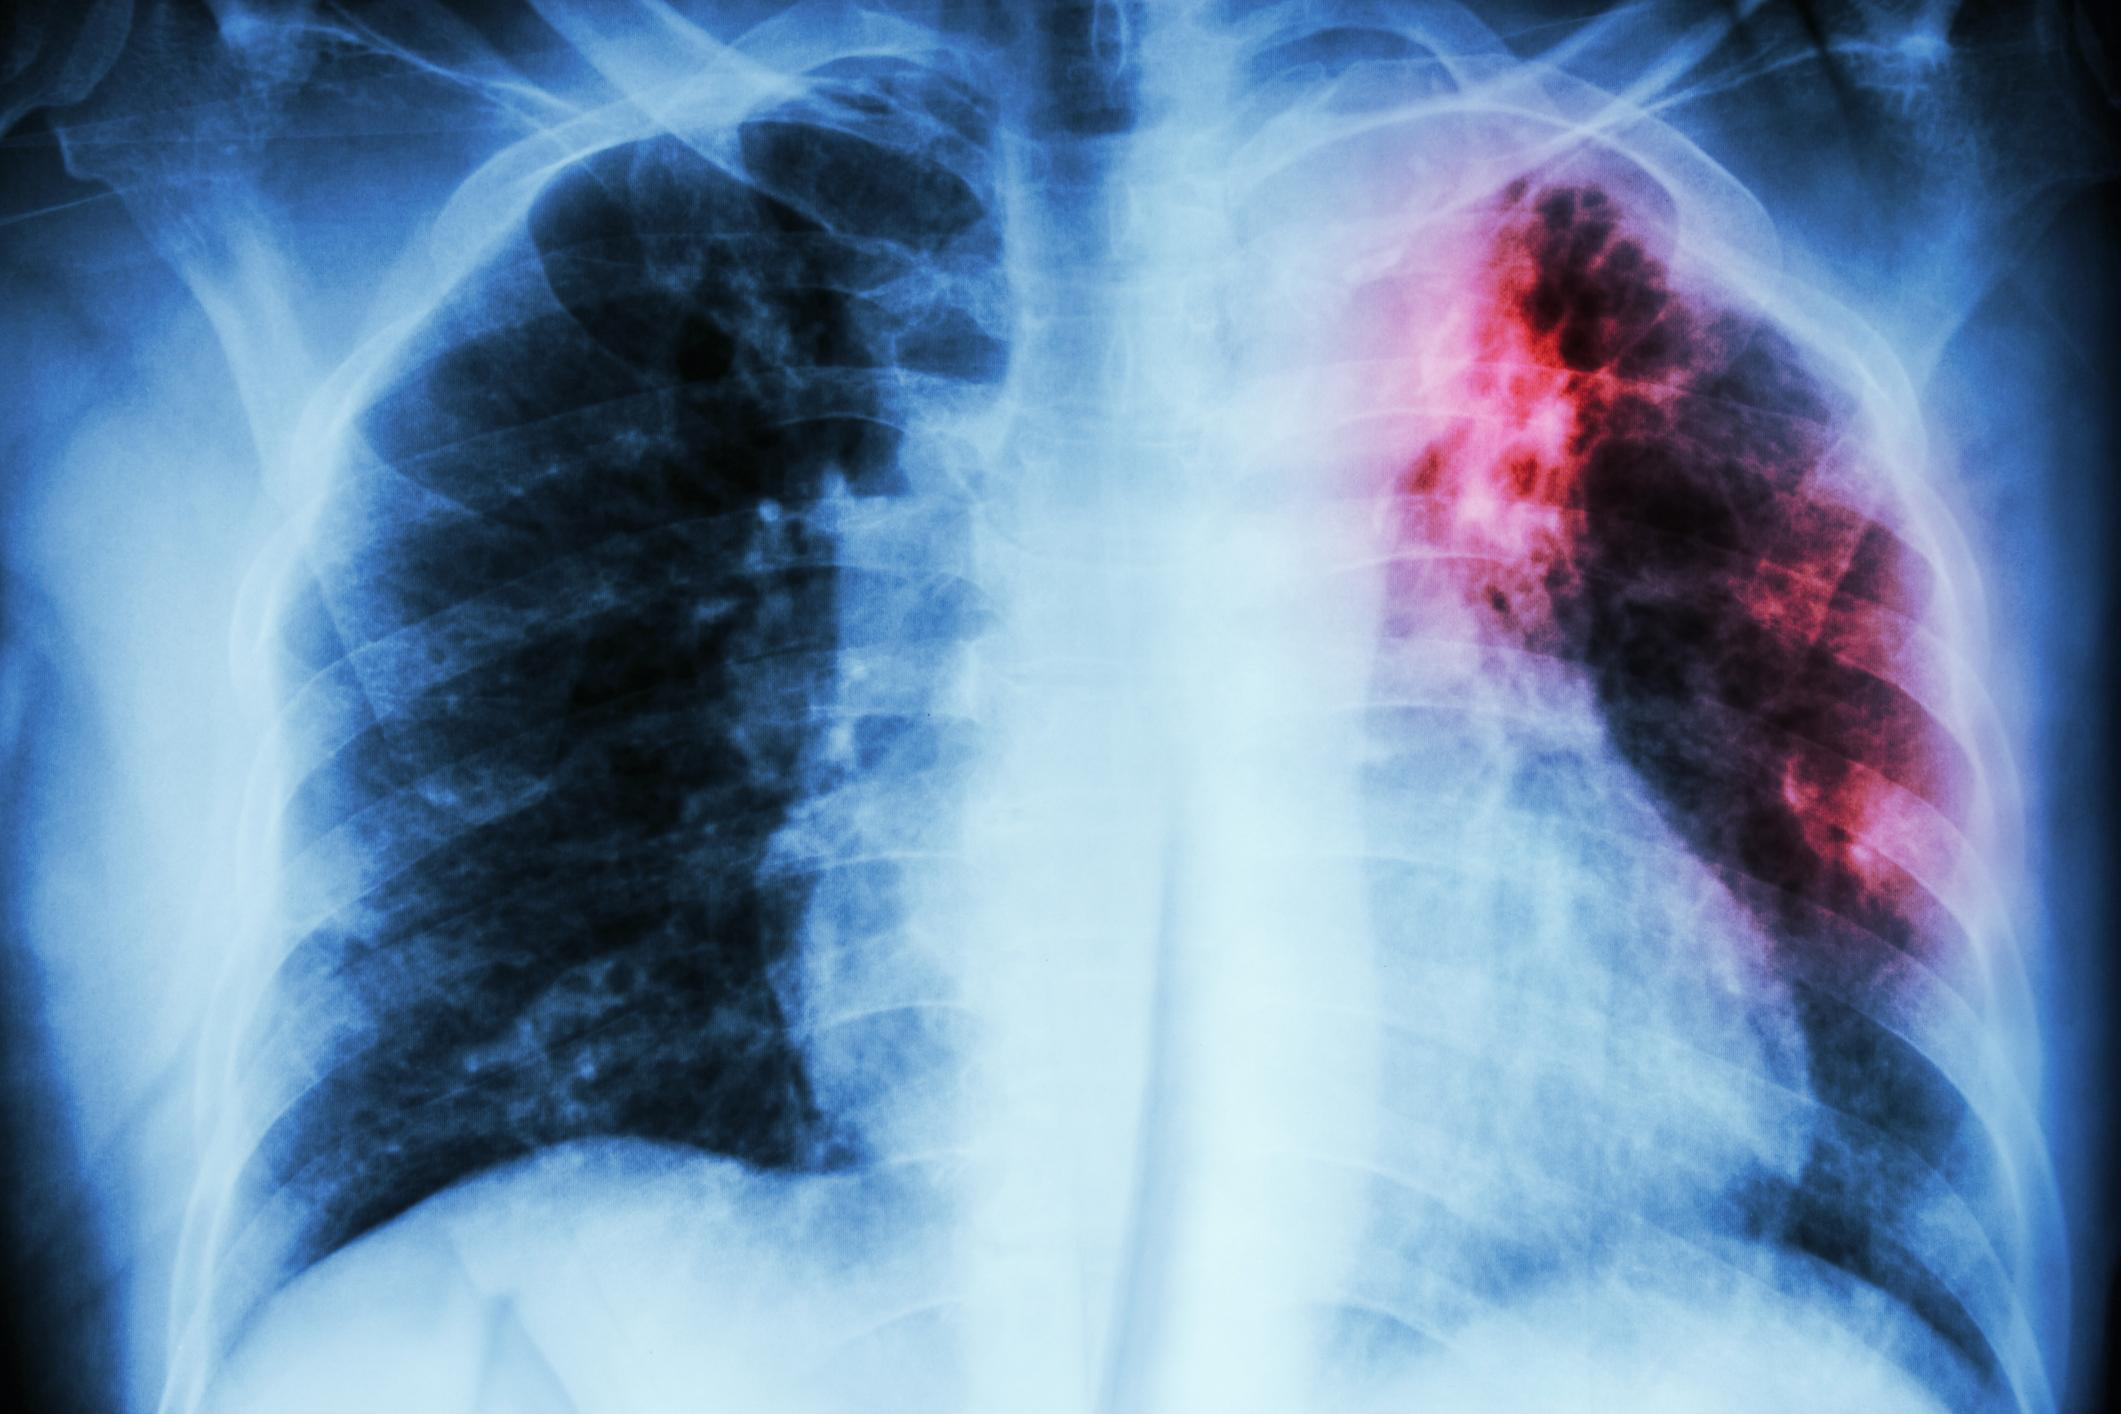

Orice persoană care are simptome sugestive de tuberculoză (mai ales tusea persistentă) trebuie să se prezinte la medic. De obicei, i se recomandă un examen radiologic pulmonar care poate pune în evidenţă modificări care pot fi date de tuberculoză. "Spre deosebire de gripă, tuberculoza este mult mai puţin contagioasă, transmisia făcându-se, în special, pe cale aeriană. Din zece persoane infectate, două, cel mult trei, fac boala. Orice organ poate fi afectat de bacilul Koch (bacteria responsabilă de apariţia tuberculozei - n.r.), dar, cel mai frecvent, microbul afectează plămânul", explică medicul pneumolog Marta Lefter.